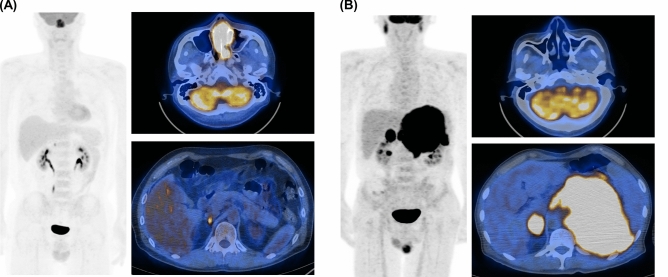

Finally, each case was classified based on FDG PET/CT pattern and volumetric parameters useful for discerning IS type. Representative PET/CT images of patients that displayed single and multiple IS-favoring findings are illustrated in Figs. 2A,B, respectively.

Figure 2.

Representative PET/CT images of ENKTL patients. (A) Maximum intensity projection (left) and transaxial fusion PET/CT (right) images of a 50-year-old male showing tumor with highest SUVmax in the nasal cavity (MTV = 43, TLG = 318). The patient had a single IS-favoring PET pattern (small adrenal FDG lesion) and was confirmed to have IE-A subtype. (B) Maximum intensity projection (left) and transaxial fusion PET/CT (right) images of a 56-year-old male with tumor lesions in adrenal glands and testis. The patient had normal nasal cavity uptake but high MTV and TLG on adrenal lesions. This case had all four IS-favoring PET patterns and was confirmed to have IS subtype.